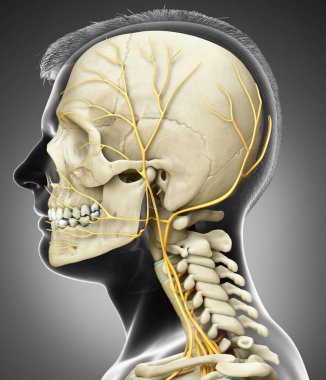

iskelet adam yan görünüm baş ve sinir sistemi

resimlemeİnsanSağlıksağlıklıYaşamkanSağlık hizmetleriTıbbiboğazıçizgi filmsemboldişlerKardiyolojikalpnabızgövdeÇizimbiyolojiBilimbölümgemigerçekçiGöğüsorgBilimselanatomidiyagramPompaGergintedavülarterAtriumApexanatomikSinirlerdolaşımaortkoronerventrikülİnsan Vücududamar sistemiPulmoner fizyolojisiFiziksel bölümdolaşımı kanAnatomi gözlerBenzer İçerikler